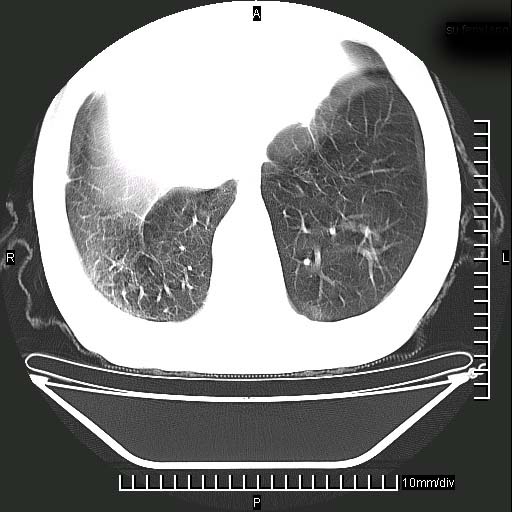

标题: CT24043:胸部增强:男性,60岁

既往肺结核,近10几天,咳嗽,咳痰,右侧胸痛,疼痛较明显,右上肺斑块考虑结核灶胸膜粘连,增强,可惜动脉期没有定好,未见强化,可延迟4分后又见较明显强化,中心见低密度影,如果说结核是边缘强化,可这个灶强化的面积挺大的,让人很挠头。

延迟4分后

[img][/img]